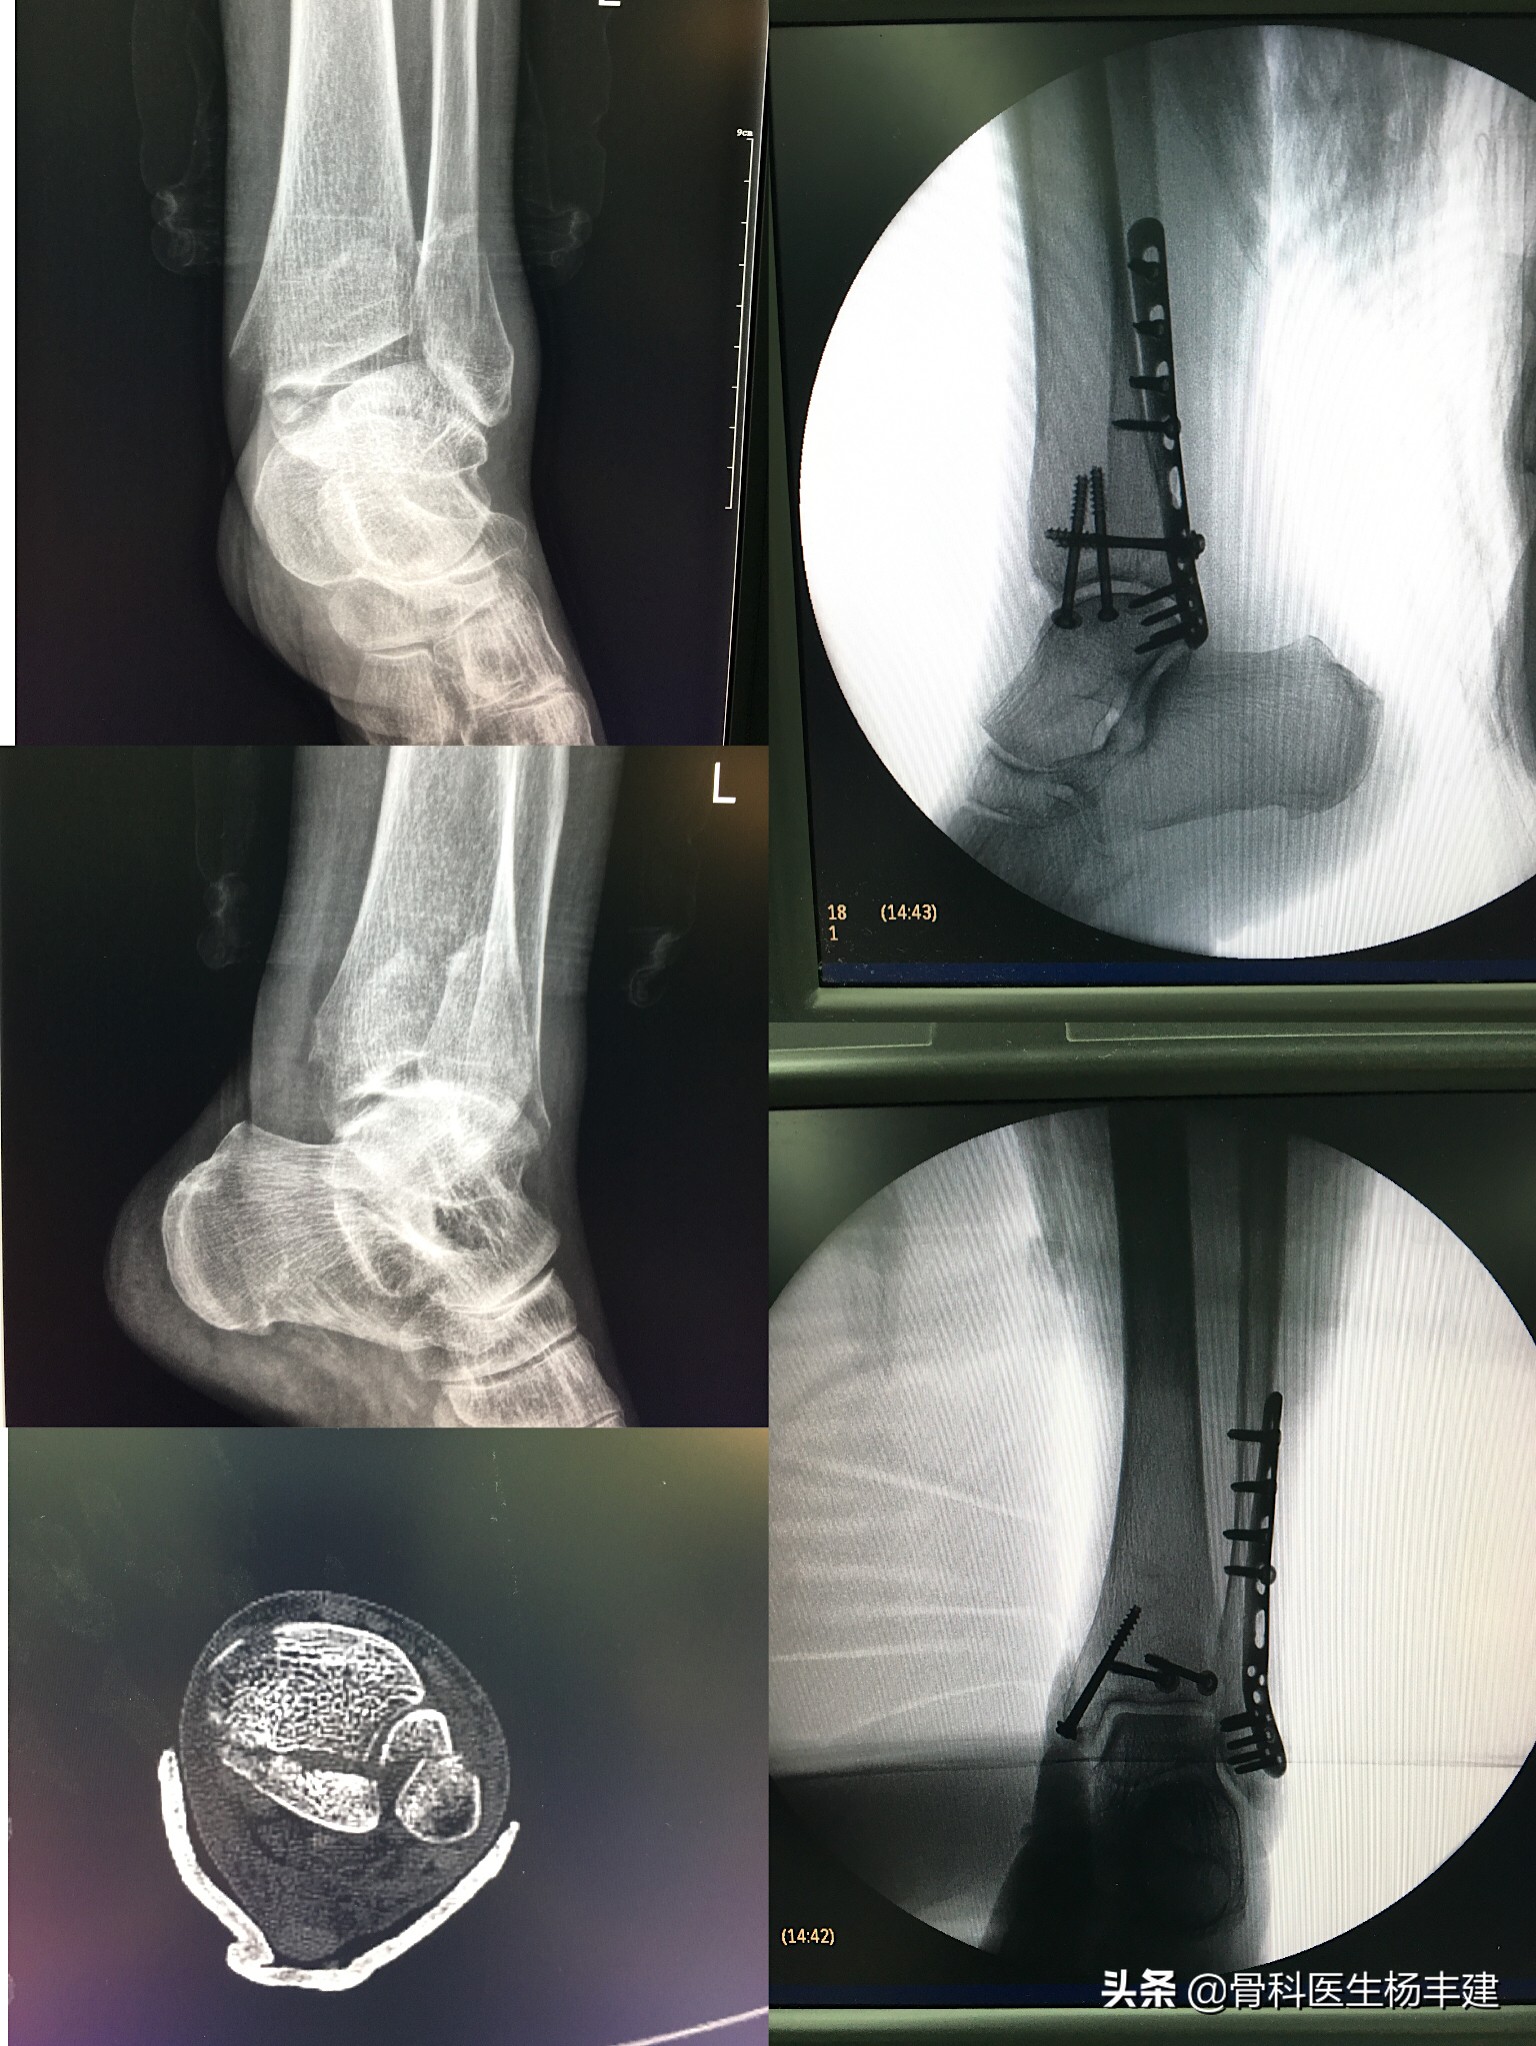

踝关节内骨折,要求完全的复位,牢固固定,早期活动锻炼